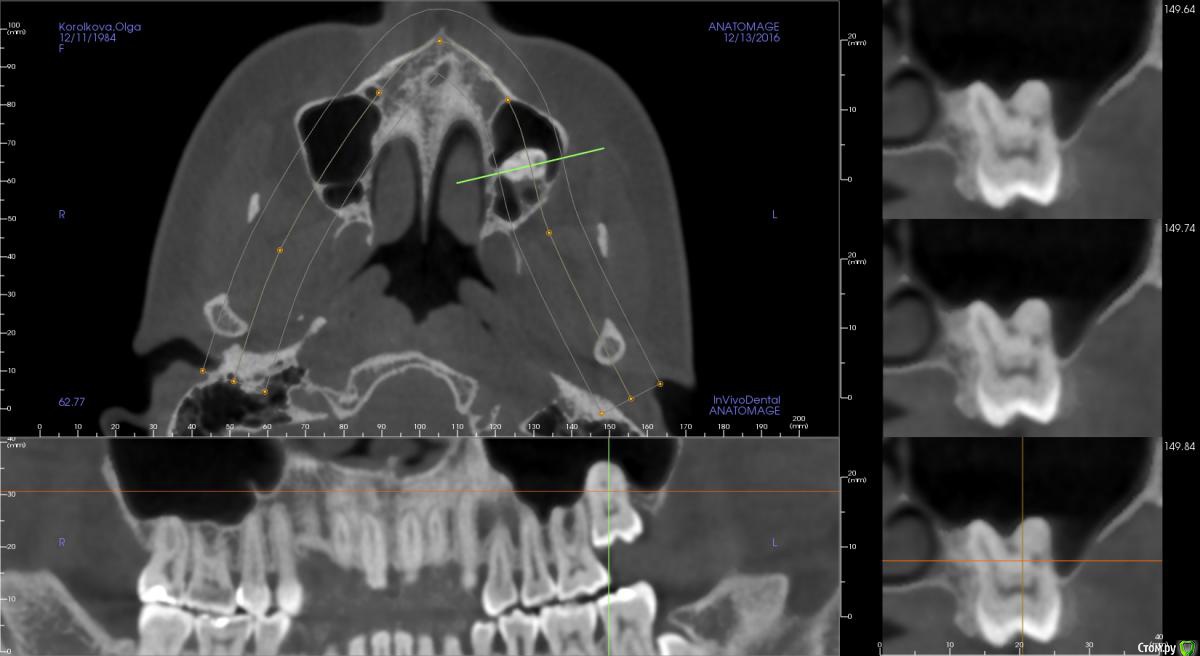

sus Опубликовано 13 декабря, 2016 Автор Поделиться Опубликовано 13 декабря, 2016 (изменено) И снова здравствуйте! И опять срочный вопрос! Итак, пришло время решать насчет семерки. За это время она сама так и не спустилась, так что все предположили ankylosis и отсутствие возможности вытянуть ее, даже сломав "мостики" и потянув брекетами. Только что сделали томограмму, вот такие результаты. Хирург говорит, что для него опция номер один - это полное удаление, но есть шанс перфорации синуса и необходимости повторной операции, если "подлатывание" в процессе удаления не поможет (он хотел что-то положить туда, забыла, коллаген, что ли). Второй вариант -коронэктомия. Мне по прочтении ряда статей казалось, что это как раз самый популярный и безопасный способ решения в такой ситуации. Но хирург уверяет, что оставшиеся корни вполне могут инфицироваться, а через них - и синус, и он бы предпочел делать так только в ситуации невозможности удалить зуб целиком (если он слишком крепко "прирос"). Но можно и сделать так, если я хочу, поскольку это более консервативно. Итак, что мне выбрать? Или при таких рисках вообще не трогать его: сейчас единственная причина удаления - это торчащий над слизистой кусочек коронки, и, соответственно, риск инфицирования через карманы вокруг. По томограмме, наверное, видно, что сам зуб пока вроде здоров (а торчит он так уже лет двадцать). И бонусом академический вопрос, неужели зуб мог так прирасти за четыре года (если тогда хирург, подергав его после "вскрыаания", утверждал, что у зуба нормальная мобильность). Мне казалось, что прорастание должно происходить на более ранних стадиях развития. Хирургия запланирована на пятницу, поэтому очень хотела бы все понять как можно раньше. Спасибо вам большое за внимание! Изменено 13 декабря, 2016 пользователем sus Ссылка на комментарий